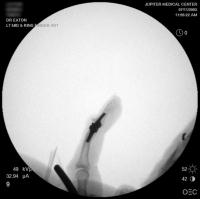

Final implant radiographs.

The implant in place. The approach was similar to the bayonette exposure  demonstrated in  this case.